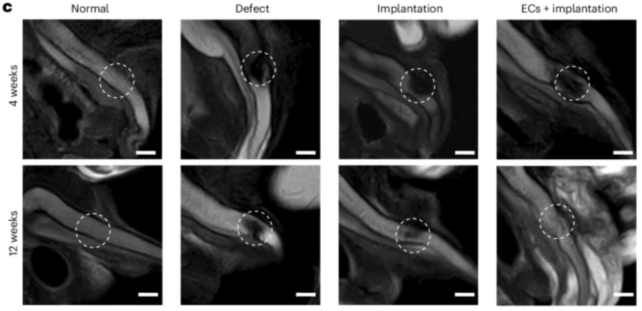

이 임플란트는 음경 해면체라고 알려진 음경의 일부를 모방하도록 설계되었으며, 길이는 2.46인치(62.5mm)입니다.

연구팀은 토끼와 돼지를 대상으로 연구를 진행했고, 인상적인 결과를 얻었습니다.

음경 조직이 손상된 돼지에게 이 임플란트를 시술한 결과, 발기가 가능했을 뿐만 아니라, 생식력 도 향상되었습니다 .

연구원들은 임플란트의 효과를 시험하기 위해 발기 부전이 있는 수십 마리의 돼지와 토끼에게 임플란트를 이식했습니다.

놀랍게도, 그들은 이 임플란트가 동물들의 발기 능력을 향상시켰을 뿐만 아니라, 번식력도 향상시켰다는 것을 발견했습니다. 예를 들어, 이식을 받기 전에 음경 조직이 손상된 돼지의 생식 성공률은 20%였습니다.

하지만 임플란트 수술을 받은 후 성공률은 100%로 뛰어올랐습니다.

연구팀은 '이번 연구에서 우리는 체외에서 발기 기능을 재현할 뿐만 아니라, 체외 이식을 통해 해면체 결손이 생긴 토끼와 돼지에서 정상적인 음경 발기 형태와 생식 기능을 회복시키는 역동적인 음경 해면체 모델을 만들었다'고 결론지었습니다.